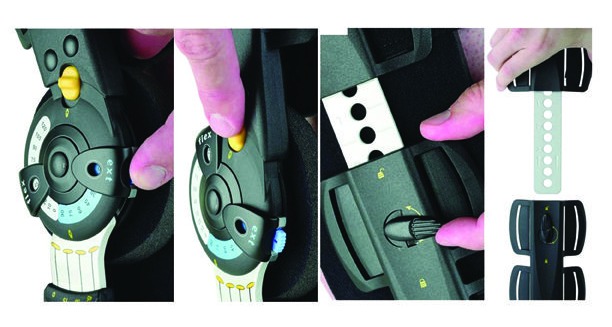

Orthèse articulée ROM- Innovator DLX

Innovator DLX - Orthèse articulée ROM post-op/post blessure pour le genou. Jusqu'à 69 cm (27") de circonférence. Genou gauche ou droit.